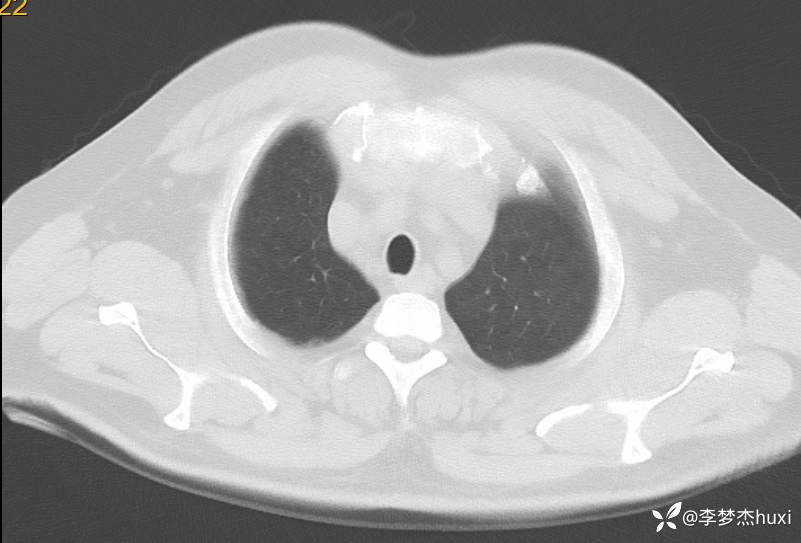

男性51岁,乏力伴胸闷、憋气4天入院,诊断可以秒杀且过目不忘

男, 51 岁,主因乏力伴胸闷、憋气4天于2024-06-11 11:57入院。

1.现病史:患者中年 男,患者缘于入院前4天无明显诱因出现乏力,伴胸闷、憋气,无咳嗽,咳痰,无发热,无咽痒,无咯血,无鼻塞、流涕,无发热,无恶心、呕吐,无腹痛、腹泻,无尿频、尿急、尿痛,无血尿及腰背部疼痛,院外查血常规:白细胞数目11.52x109/L,中性粒细胞百分比79.9%,血红蛋白69g/L。院外未服药治疗,症状无好转,现为求进一步诊治来诊,查肝胆胰脾肾彩超:脂肪肝(轻度),脾大。急诊以“低色素性贫血”收住院。。